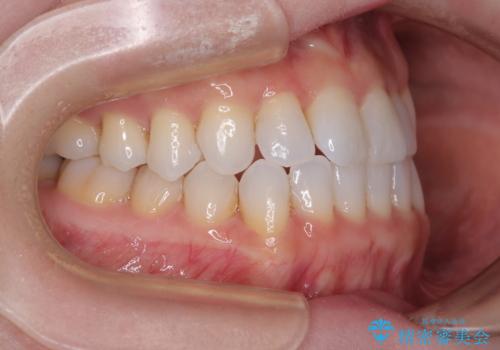

前歯のデコボコをインビザラインで綺麗に

- 上下前歯の叢生を気にして来院された患者様です。

インビザラインでの治療を希望されていて、デコボコの程度が中等度であり、安価なパッケージにて対応可能と判断されたため、インビザライン・モデレートを用いて矯正治療を行うこととしました。

インビザライン・モデレートは、製作できるアライナーの枚数に制限があるため、移動可能な量に限りがあるものの、インビザライン・ライトよりも枚数が多いため、幅広い症例に対応可能です。